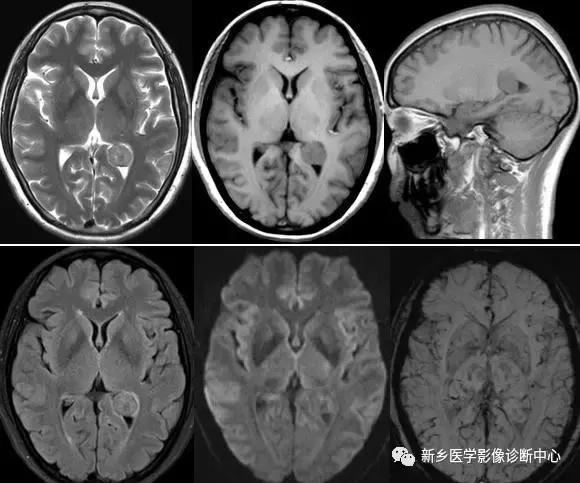

室管膜瘤(侧脑室,双侧,右侧为主,左侧囊变)

史上最全脑室解剖图谱快收藏了吧

侧脑室三角区肿瘤的诊断

侧脑室磁共振

侧脑室ct

侧脑室ct图片